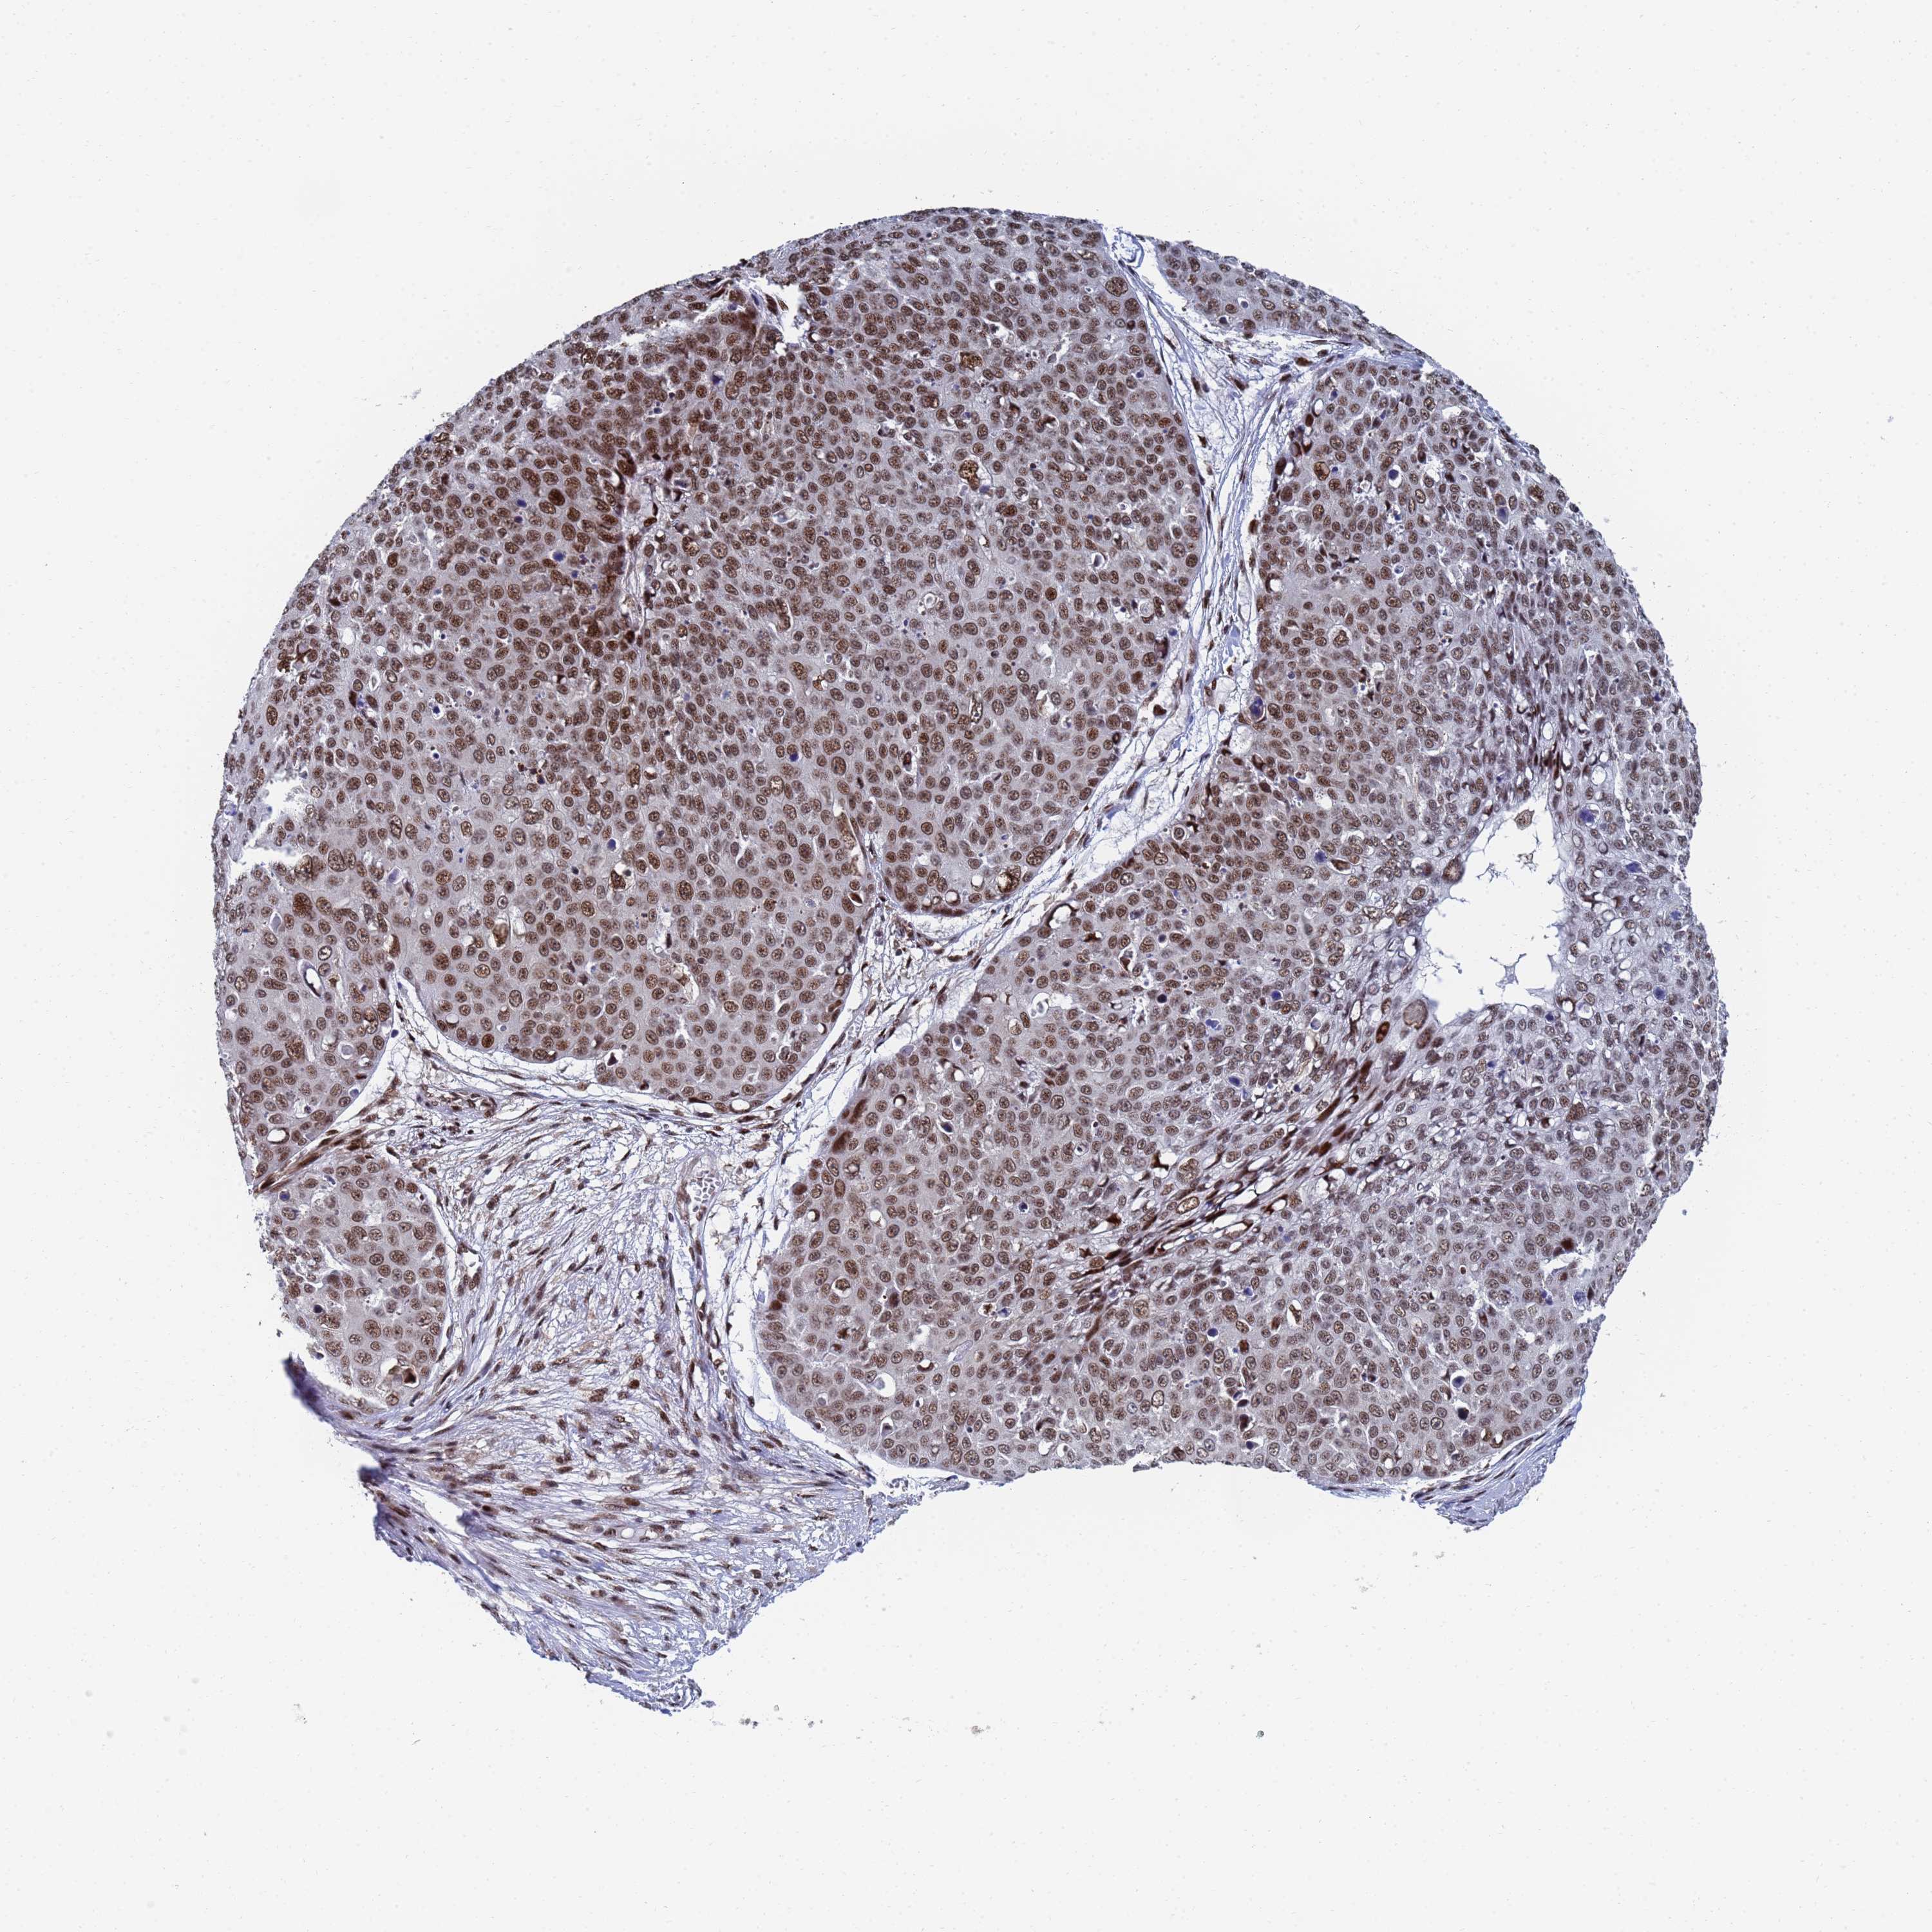

Basal cell and squamous cell cancer

SKIN CANCER - Protein expressioni

A mouse-over function shows sample information and annotation data. Click on an image to view it in a full screen mode. Samples can be filtered based on level of antibody staining by selecting one or several of the following categories: high, medium, low and not detected. The assay and annotation is described here.

Antibody stainingi

Antibody staining in the annotated cell types in the current human tissue is reported as not detected, low, medium, or high, based on conventional immunohistochemistry profiling in selected tissues. This score is based on the combination of the staining intensity and fraction of stained cells.

Each image is clickable and will lead to virtual microscopy that enables deeper exploration of all samples and also displays staining intensity scores, fraction scores and subcellular localization as well as patient and tissue information for each sample.

Antibody HPA035693

Staining

High

Medium

Low

Not detected

Intensity

Strong

Moderate

Weak

Negative

Quantity

>75%

75%-25%

<25%

None

Location

Nuclear

Cytoplasmic/membranous

Cytoplasmic/membranous,nuclear

Squamous cell carcinoma, NOS